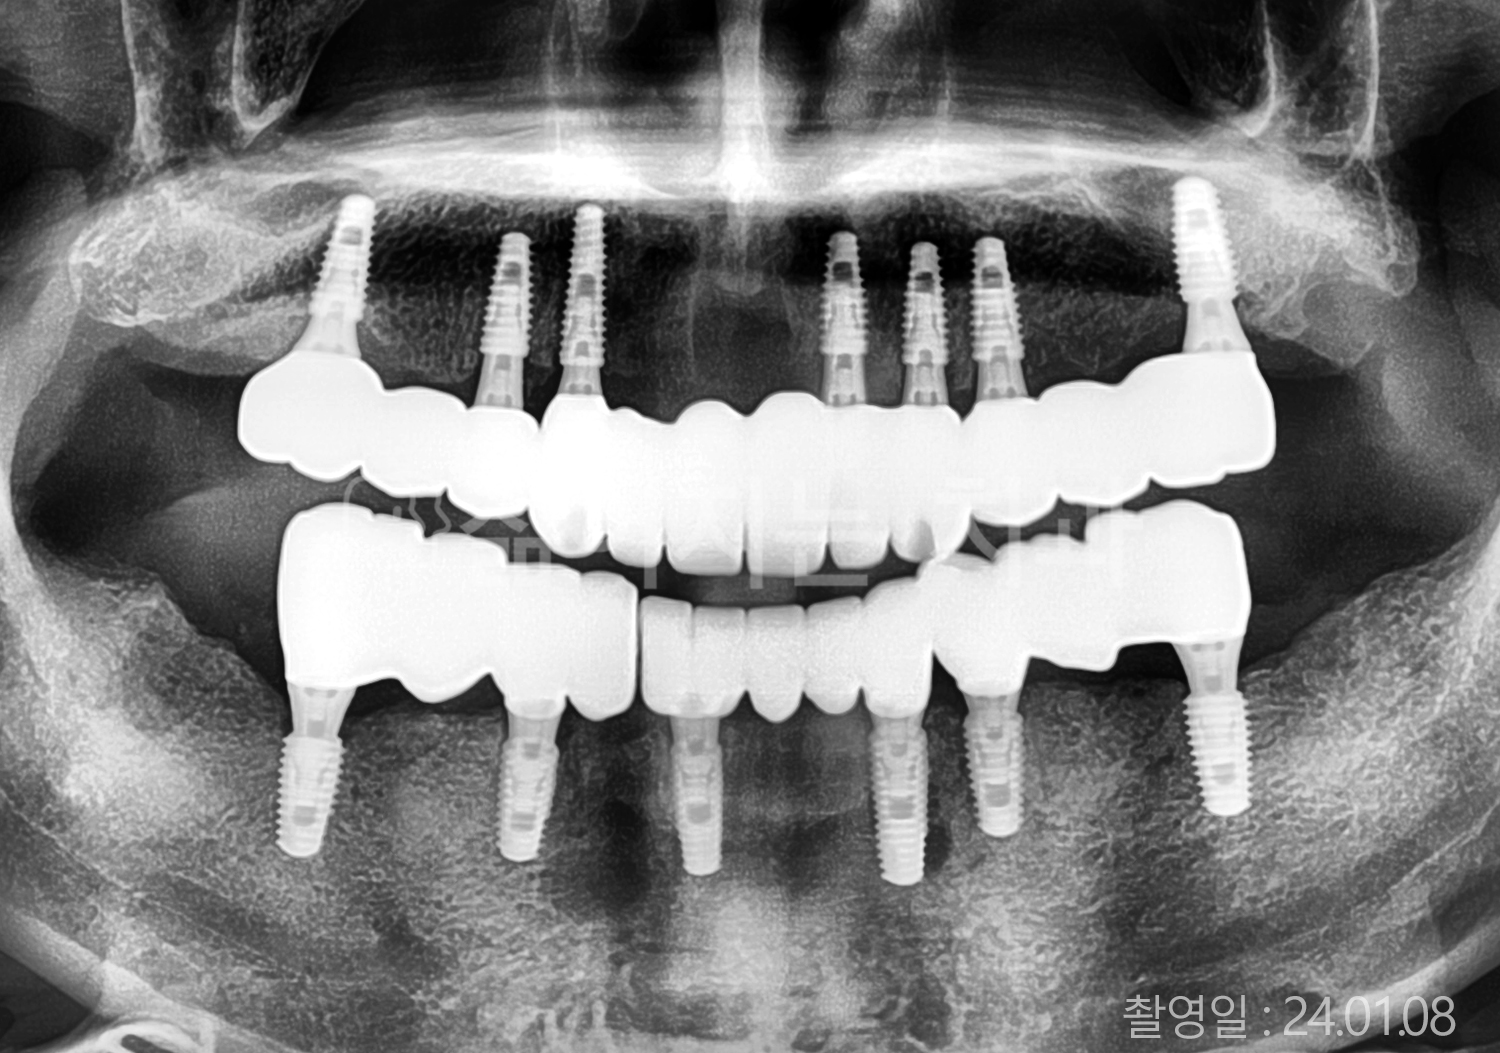

• 70대 고혈압, 고지혈증 전체치아 10개 이상 임플란트

• 60대 당뇨, 간염 전체치아 10개 이상 임플란트

• 80대 골다골증 전체치아 6개 이상 임플란트

• 70대 고혈압, 당뇨 전체치아 10개 이상 임플란트

• 60대 간 질환 전체치아 10개 이상 임플란트

• 60대 전체치아 10개 이상 임플란트

• 70대 전체치아 10개 이상 임플란트

• 50대 전체치아 10개 이상 임플란트

• 60대 고혈압, 고지혈증 전체치아 10개 이상 임플란트

• 40대 고지혈증, 뇌혈관 질환 전체치아 10개 이상 임플란트